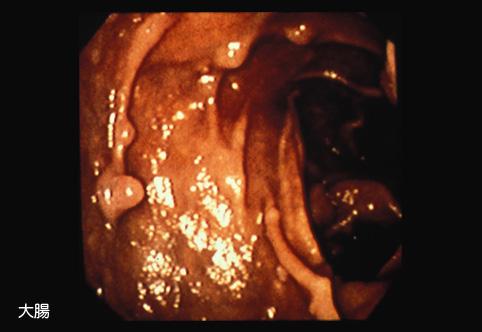

A case of Peutz-Jeghers syndrome which was associated with advanced mucinous adenocarcinoma in the small intestine.

Tumor-like lesions/Peutz-Jeghers syndrome

Large intestine(Colon)/Sigmoid colon

Endoscopy

1 - 9